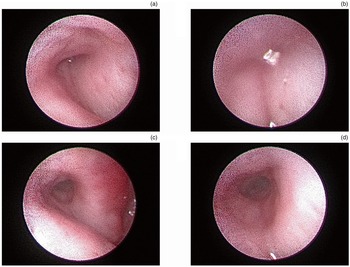

The Eustachian tube video endoscope instrument was inserted into the Eustachian tube to observe the position reached, with the supporting balloon installed in the front section (soft section) of the endoscope. We encountered no technical difficulties in identifying the pharyngeal Eustachian tube orifice in the nine human cadavers. The endoscope tip was advanced into the pharyngeal ostium of the Eustachian tube, and the Eustachian tube cavity was examined (Figure 3a). Then, the balloon catheter was gently advanced through the working channel with the endoscope until the narrowest position of the Eustachian tube was reached (Figure 3b).

Figure 3. The pre- and post-operative Eustachian tube on Eustachian tube video endoscopy. (a) The pharyngeal ostium of the Eustachian tube on Eustachian tube video endoscopy. (b) The narrowest position of the Eustachian tube on Eustachian tube video endoscopy. (c) The post-operative Eustachian tube cavity on Eustachian tube video endoscopy. (d) The narrowest segment of the post-operative Eustachian tube on Eustachian tube video endoscopy.

In all cases, the catheter and balloon were correctly positioned, as confirmed by the endoscope video. After being correctly positioned in the ostium, the balloon catheter was advanced by an assistant without resistance. After the balloon was dilated, it was removed from the soft segment of the Eustachian tube video endoscope, and then the Eustachian tube video endoscope was pushed forward to observe the state of the Eustachian tube cavity. The narrowest segment of Eustachian tube was clearly observed (Figure 3c–d).